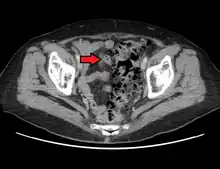

CT scan showing extensive diverticulosis of the sigmoid colon

Diverticular disease

• Contrast CT is the investigation of choice in acute episodes of diverticulitis and where complications exist.